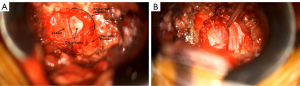

Most muscle over the intertransverse membrane was retracted by the lateral blade. Any residual was then removed with rongeurs or equivalent until the intertransverse membrane (Figure 3A) was clearly identified. Any vessels coursing medial to lateral across it were divided after bipolar cautery. The muscle/membrane was opened, with any of a blunt hook, knife, rongeur or punch. Immediately deep to the intertransverse membrane, fat and fibrous tissue were encountered (Figure 3B), then branches of the pars vessel, which were divided and cauterised immediately superficial to the nerve root (Figure 3C). Due to vessel branches in this area, it often had to be cauterised several times.

Once in this deeper space and with good vision (with operating microscope), a Watson Cheyne or blunt hook was used to confirm the anatomy. Starting distally and working off the transverse process of the lower level onto the side of the lower vertebra and then onto the disc. By staying inferior we found the disc prolapse was usually encountered before the nerve, as most commonly the disc pushes the nerve root superiorly (Figure 4A). Occasionally the nerve was found to be tented tightly over the prolapse and very thinned out just lateral to the ganglion. If uncertain, we dissected further medially to find the medial edge of the root, confirmed by easy passage of a hook back into the foramen below the root.

Having identified the disc coming from below the root, a ball hook or similar was used to confirm the root. It was often identified by feel, before it was clearly visualised. Once identified and mobilised, the assistant could gently retract the root superiorly to provide safer access to the disc (Figure 4B). However, this was sometimes difficult due to the tight working space between the lower pedicle and exiting nerve root. Often the surgeon retracted the root with a Rhoton sucker, while removing the disc prolapse with a rongeur, or ball hook.